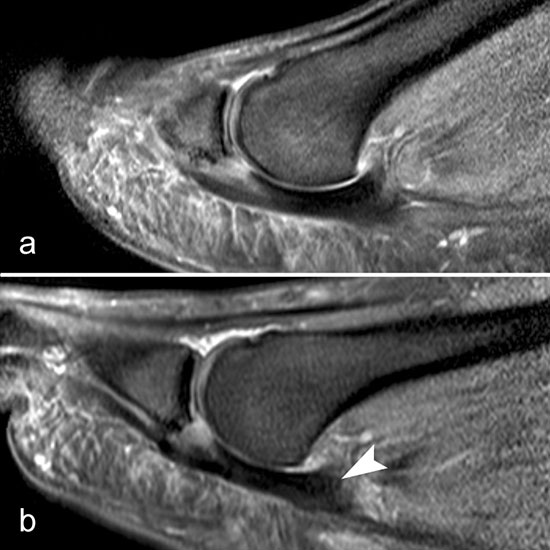

Rupturen ereignen sich am häufigsten an den distalen Insertionen der Metatarsophalan­gealgelenke (Abb. 5), etwas seltener auf Höhe der Metatarsaleköpfchen. Die Läsionen können sehr umschrieben sein, quer durch die gesamte plantare Platte reichen und sich sogar bis in die Kollateralbänder fortsetzen 1. Rupturen der plantaren Platte finden sich am häufigsten an der zweiten Zehe, die dritte Zehe ist etwas seltener betroffen. An der vierten und fünften Zehe sind die Läsionen sehr ungewöhnlich. Rupturen der pantaren Platte führen häufig zu einer ausgeprägten Weichteilreaktion, die nicht als Morton-Neurom fehlgedeutet werden sollte (Abb. 6) und zur Ausbildung einer Neo-Bursa führen können (Abb. 7).

Ein Sonderfall stellt die Großzehe dar: Hier verstärken die Sesambeine, das intersesamoidale und die sesamophalangealen Bänder die Gelenkkapsel. Der faserknorpelige Anteil der plantaren Platte distal der Sesambeine ist oft nur sehr dünn. Verletzungen dieser plantaren Kapselstrukturen des Großzehengrundgelenkes werden auch als „turf toe“ bezeichnet

(Abb. 8).

Zwischen der plantaren Platte und der Grundphalanx ist in der Mittellinie des Gelenkes ein kleiner Rezessus vorhanden (Abb. 9).

Dieser flüssigkeitsgefüllte Raum darf nicht als Ruptur der plantaren Platte fehlinterpretiert werden 23. Verletzungen der plantaren Platte erfassen immer auch den medialen oder lateralen Zügel.